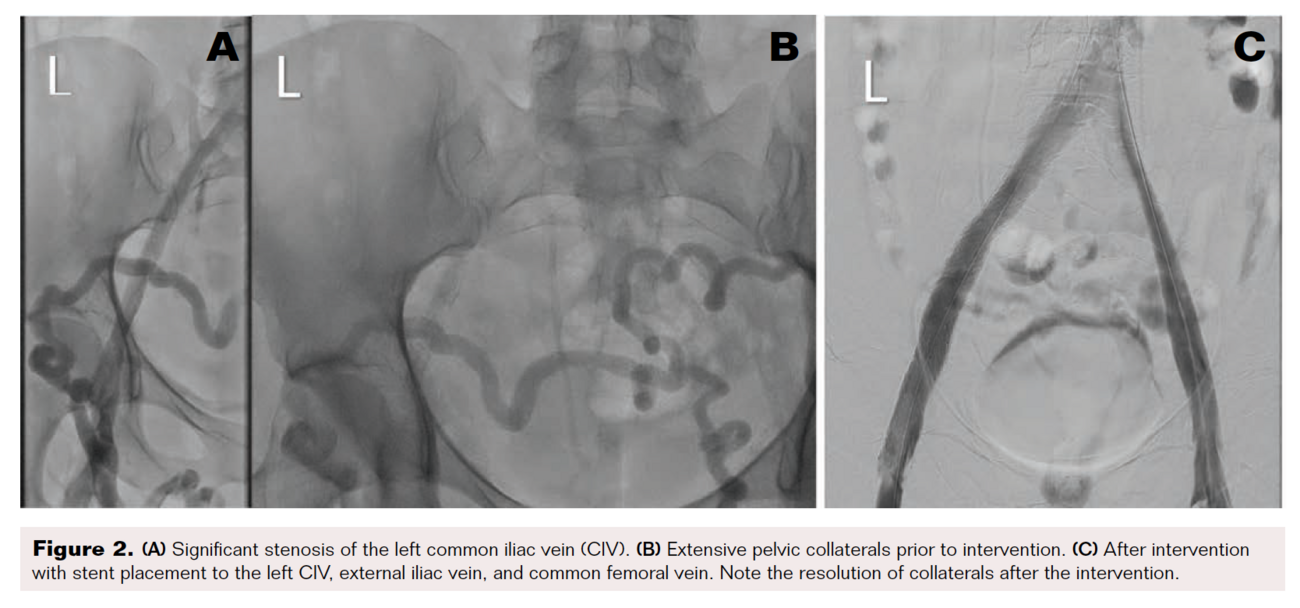

A 39-year-old woman with a history of recurrent deep vein thrombosis (DVT), pulmonary embolism (PE), and protein C deficiency on oral anticoagulation (OAC) was referred to our clinic for chronic bilateral lower extremity swelling, redness, and varicose veins. She was initially diagnosed with DVT and PE in 2003, for which she was on OAC with warfarin. Her warfarin was discontinued 6 months later, and she did well until 2018 when she had a recurrent DVT and PE following an 8-hour plane ride. At that time, a workup revealed a protein C deficiency, and she had been on OAC with apixaban 5 mg twice daily ever since. Her leg swelling, redness, and pain became severe a few weeks before presentation, which was aggravated by standing for long periods. She also complained of frequent dyspareunia and periodic pelvic pain. On physical examination, she was noted to have varicose veins on both legs, 2+ pedal edema up to the level of the thigh, and redness in both legs. We ordered a venous ultrasound (US) of the lower extremity to assess for reflux and to rule out DVT. We ordered a magnetic resonance angiography (MRA) with the suspicion of a central venous obstruction and PCS. Her US showed a chronic, nonocclusive thrombus in the left common femoral vein (CFV). Her MRA showed effacement of the proximal left iliac vein by the right common iliac artery, which was consistent with May-Thurner syndrome (Figure 1). In addition, the MRA showed varices of the anterior pelvic wall. We performed venography with intravascular US (IVUS)-guided percutaneous transluminal angioplasty (PTA) and stent placement. US-guided access was obtained from both right and left popliteal veins, and 8 Fr sheaths were inserted. Contrast venography was performed to both the deep femoral and iliac veins, demonstrating vessel patency throughout with visually apparent luminal narrowing in the left iliac vein. IVUS confirmed a 40% compression of the right external iliac vein (EIV) and a diffuse 80% fibrotic stenosis of the left common iliac vein (CIV) to CFV (Figure 2A). Extensive pelvic collaterals were also noted (Figure 2B). We performed PTA of the left CIV with a 16 mm x 40 mm Atlas Gold balloon (BD). Following balloon angioplasty, through the 8 Fr sheath, we deployed a 16 x 140 mm Zilver Vena stent from the left CIV into the EIV and deployed another 16 x 60 mm Zilver Vena stent overlapping with the first stent from the EIV into the CFV. The stents were post-dilated with the same Atlas Gold balloon, and a postprocedure venogram and IVUS showed excellent results, with complete resolution of the pelvic collaterals (Figure 2C). She was discharged home on clopidogrel 75 mg daily in addition to the apixaban 5 mg twice daily that she was already on. On a follow-up visit 1 month later, the patient reported significant reduction of her lower extremity edema, pain, and redness. On a 6-month follow-up, she reported complete resolution of these symptoms as well as pelvic pain and dyspareunia.